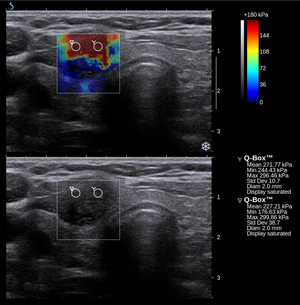

التصوير المرن